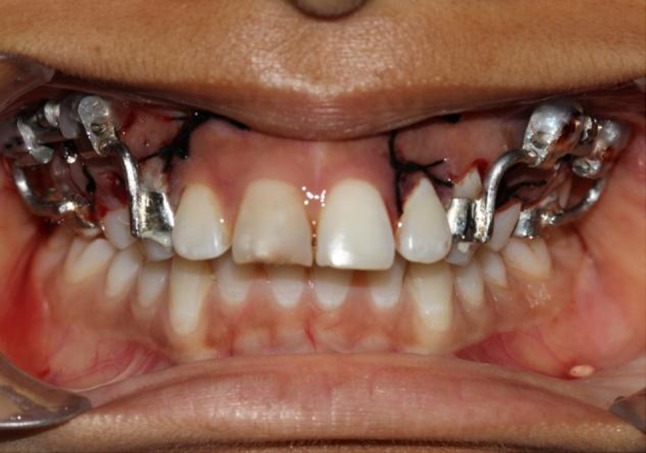

Distractors cemented bilaterally

Fig. 12.

Cemented distractors from occlusal view